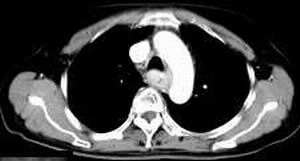

女,61岁,吞咽困难(包括开水)已久。

食道中上段癌并锁骨上窝淋巴结转移.

食道中上段中分化鳞癌伴锁骨上淋巴结转移